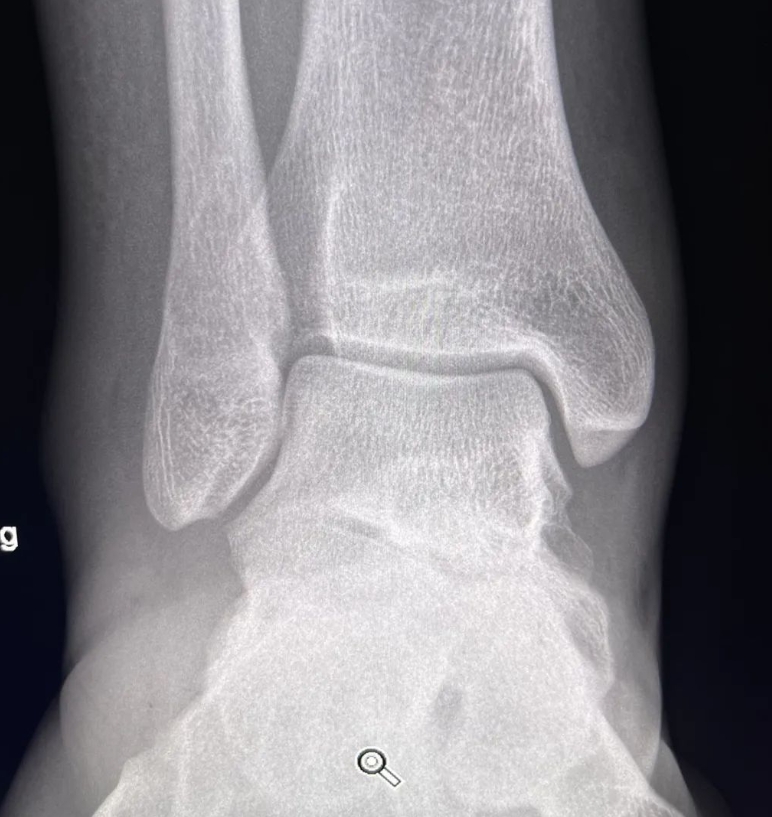

教学病例:踝关节X线片!